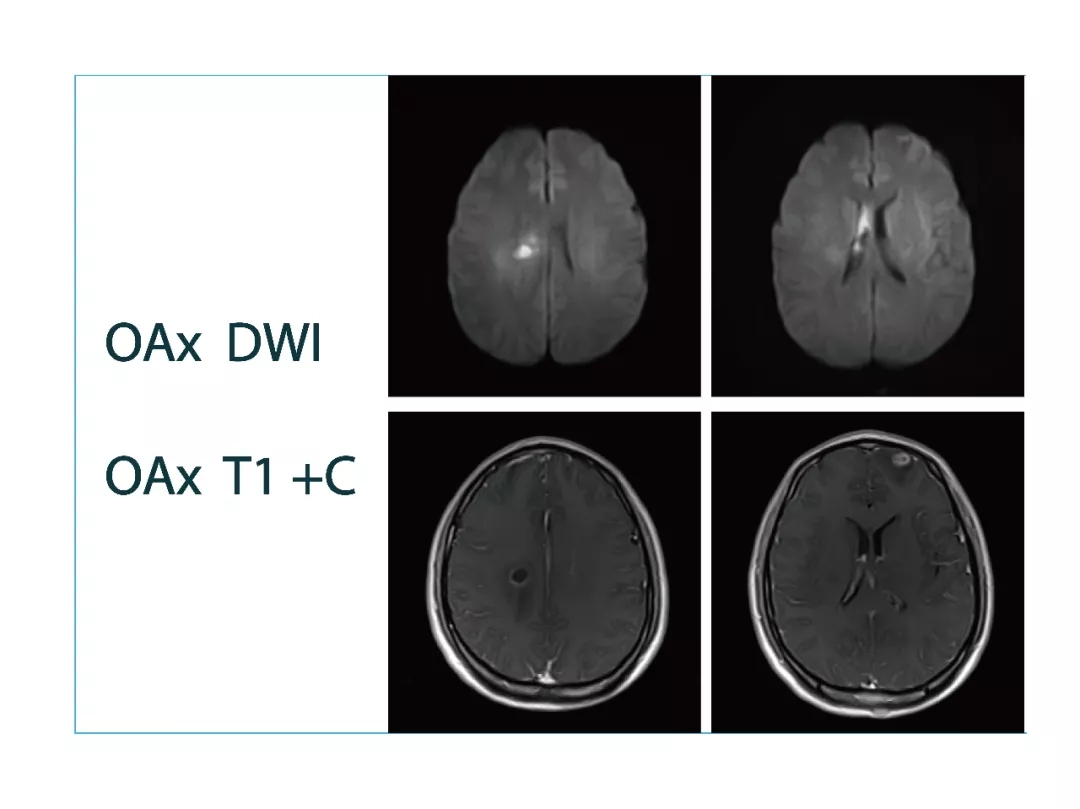

【朗润影像档案】磁共振影像病例分享(编号20180413)